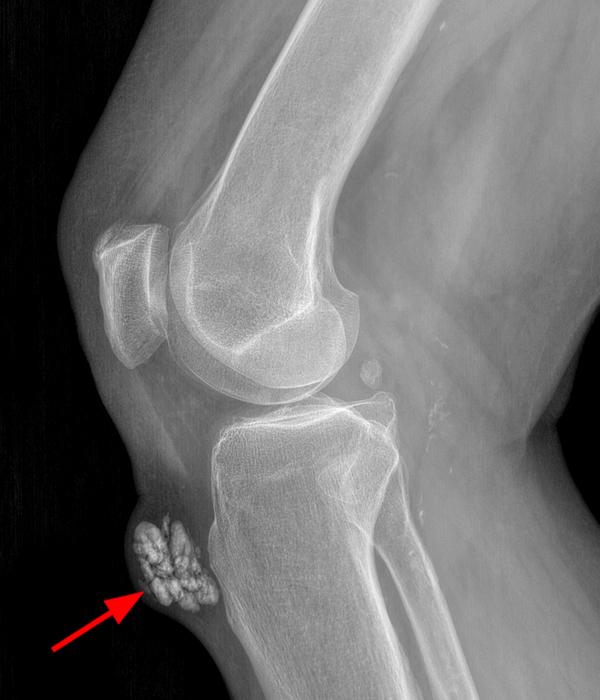

Mid 20th century Xray photograph / radiograph showing bursitis in the Septic Bursitis In The Knee treatment bursitis often gets better over time, so treatment most often aims to ease your symptoms. septic arthritis can develop when an infection, such as a skin infection or urinary tract infection, spreads through. issues related to septic bursitis are discussed here. inflammation of the bursa due to prolonged pressure, overuse, trauma or arthritis, causes excess. Septic Bursitis In The Knee.